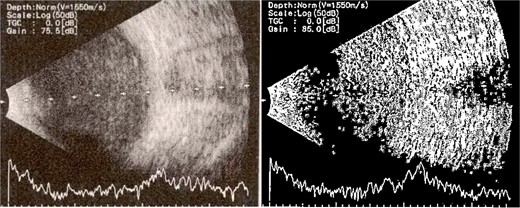

Patient 4: A 74-year-old Sudanese male visited the emergency room with severe left eye pain and loss of vision. His visual acuity was PL; examination showed hypopyon (Fig. 7). B-scan demonstrated vitritis (Fig. 8). He underwent emergency vitreous tap and intravitreal antibiotic therapy.

B-scan ultrasound demonstrating moderate vitreous echoes and vitreous abscess in patient 4.